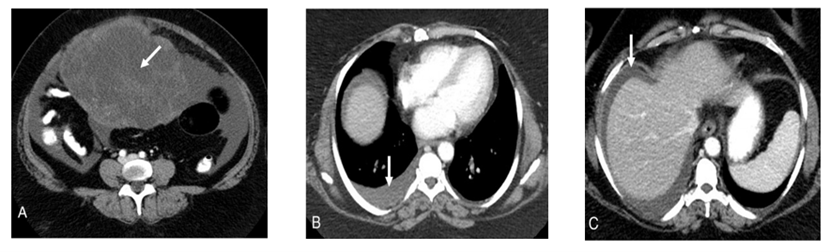

引言: 梅格斯综合征(Meigs)综合征是一种少见的妇科合并症,患者就诊时通常具有盆腹腔大肿物、合并胸腹水的症状,让我们迅速联想到了卵巢恶性肿瘤的可能性,殊不知,它其实只是一只“披了狼皮的羊”。 第一部分:病历及思考 病例线索1 患者女性,67岁 主诉:腹胀伴胸闷憋气1个月,发现盆腔肿物5天。 现病史:患者1个月前无明显诱因出现腹胀伴胸闷憋气,5天前就诊于当地医院,查妇科超声提示盆腔肿物,直径约15cm,伴大量腹水,诊断为:盆腔肿物并腹水。患者为求进一步治疗来我院。 月经及生育史:自然绝经10余年,G2P2,足月顺产2次。 既往史及家族史:既往体健,家族史无特殊。 妇科检查:双合诊:已婚经产型外阴,阴道通畅,宫颈萎缩、光滑,盆腹腔偏右侧可触及一个直径约15cm实性包块,边界较清,质硬,活动度可。因腹水较多子宫及对侧附件触诊不满意。三合诊:子宫及双附件同双合诊检查,子宫直肠窝空虚,未触及结节。 初步辅助检查: 1、血常规结果提示:白细胞:11.00*109/L,余大致正常,生化全项:白蛋白:22.1g/L,余大致正常。凝血功能、尿常规等常规化验检查未见明显异常,心电图、腹部超声未见明显异常。 2、盆腔超声提示:右下腹可见一直径约15cm低回声实性包块,边界清,其内未见明显血流信号,下腹部肠间隙可探及大片状液性暗区,最深处约12cm。 3、胸盆腹CT结果示:两侧胸腔积液,右侧显著,下腹部、盆腔可见直径约15cm团块状囊实性混杂密度影,考虑卵巢来源,腹盆腔积液。 4、肿瘤标志物:CA125、CA199、CEA等均在正常范围之内,人附睾蛋白4(HE4):194 pmol/L(我院正常范围绝经后<140pmol/L)。 思考1 老年女性,合并盆腔大肿物,伴有胸腹水,是否有“卵巢癌”可能性? 该患者肿瘤标志物尤其是CA125和CA199均在正常范围之内,但HE4数值高于正常。CA125是监测上皮性卵巢癌最重要的生物标志物之一,灵敏度较高,但特异度欠佳(灵敏度为81.4%、 特异度为56.8%)。而CA199则是诊断卵巢黏液性癌的敏感指标。HE4是近年来被广泛关注的新型肿瘤标志物,正常情况下,该标志物在机体中的表达水平极低,但在卵巢癌患者的血清中却呈现较高的表达水平,而且与CA125相比,对于临床分期为Ⅰ期卵巢癌患者也具备更高的特异性。因此结合该患者肿瘤标志物的情况及CT结果,不能除外卵巢癌的可能性。 除此之外,有没有可能是结核? 腹盆腔结核患者可有原发不孕、发热盗汗等结核病特异表现,但仍有大多数患者是以盆腔包块和腹腔积液为主要首发症状就诊的。盆腔结核患者的肠管、大网膜与子宫附件粘连可形成实性包块,结核病灶的渗出也可表现为囊性包块。盆腔结核患者的腹水多为草绿色渗出液,以淋巴细胞为主,其内可能找到结核杆菌,当多次细胞学检查未发现癌细胞时,要考虑结核的可能。 病例线索2 继续完善相关辅助检查: 腹水找癌细胞:(-); 胃肠镜未见明显异常; PPD实验:(-)。 思考2 患者PPD实验阴性,基本除外了结核的可能性,胃肠镜检查未见明显异常,暂不考虑胃肠道转移瘤,结合CT考虑来源于卵巢的肿瘤可能性最大。腹水未查到癌细胞,又有大量的胸腹水。 有没有可能是Meigs综合征?如果是Meigs综合征,是真性Meigs综合征还是假性Meigs综合征? 两者因为都具有相似的三联征(包括卵巢肿瘤、胸水、腹水),临床上并不容易区分,最终诊断需要依靠手术病理学检查。鉴于患者一般情况较好(无基础性疾病,白蛋白>3.5g,ECOG评分0分),为了进一步明确诊断,在充分的评估后决定进行手术探查。 病例线索3 全麻下行剖腹探查术,术中见大量腹水,右卵巢肿物,直径约15cm,边界清,质硬,与周围组织无粘连,子宫及左侧附件未见明显异常,行右侧附件切除术,送术中冰冻,术中快速冰冻病理结果为卵泡膜-纤维瘤。因患者已绝经,建议其行全子宫+双附件切除术,遂继续行全子宫+左侧附件切除术。 思考3 卵巢卵泡膜-纤维瘤组肿瘤(OTFG)属于性索间质肿瘤,占所有卵巢肿瘤的1%-4%,多为良性,好发于围绝经期和绝经后患者。根据卵泡膜细胞和纤维母细胞含量的不同病理分为3个亚型: (1)卵泡膜细胞瘤,几乎均由卵泡膜细胞构成; (2)卵泡膜纤维瘤,由卵泡膜细胞和纤维母细胞按不同比例构成; (3)纤维瘤,均由纤维母细胞构成,几乎不含卵泡膜细胞。 该肿瘤组织学分化特点有多向重叠, 病理学也很难精确分类,WHO建议将其称为卵泡膜细胞瘤-纤维瘤组肿瘤,该患者尽管术前考虑不能除外晚期上皮性卵巢癌,剖腹探查的结果及术中冰冻病理结果提示我们,该病例很大可能是Meigs综合征,鉴于OTFG良好的预后,这位患者无疑是幸运的。 病例线索4 患者术后病理结果汇报:(右侧)卵巢卵泡膜纤维瘤。子宫及左侧卵巢、双侧输卵管均为良性病变。 术后1个月随访情况:患者恢复良好,复查盆腔超声呈术后改变,未见积液。胸部CT显示双肺未见明显异常,未见明显积液。 思考4 术后病理作为金标准,证实了该患者卵巢卵泡膜纤维瘤的诊断,结合其术前影像学提示的大量胸腹水,以及术后胸腹水的迅速消失,Meigs综合征的诊断确诊无疑。